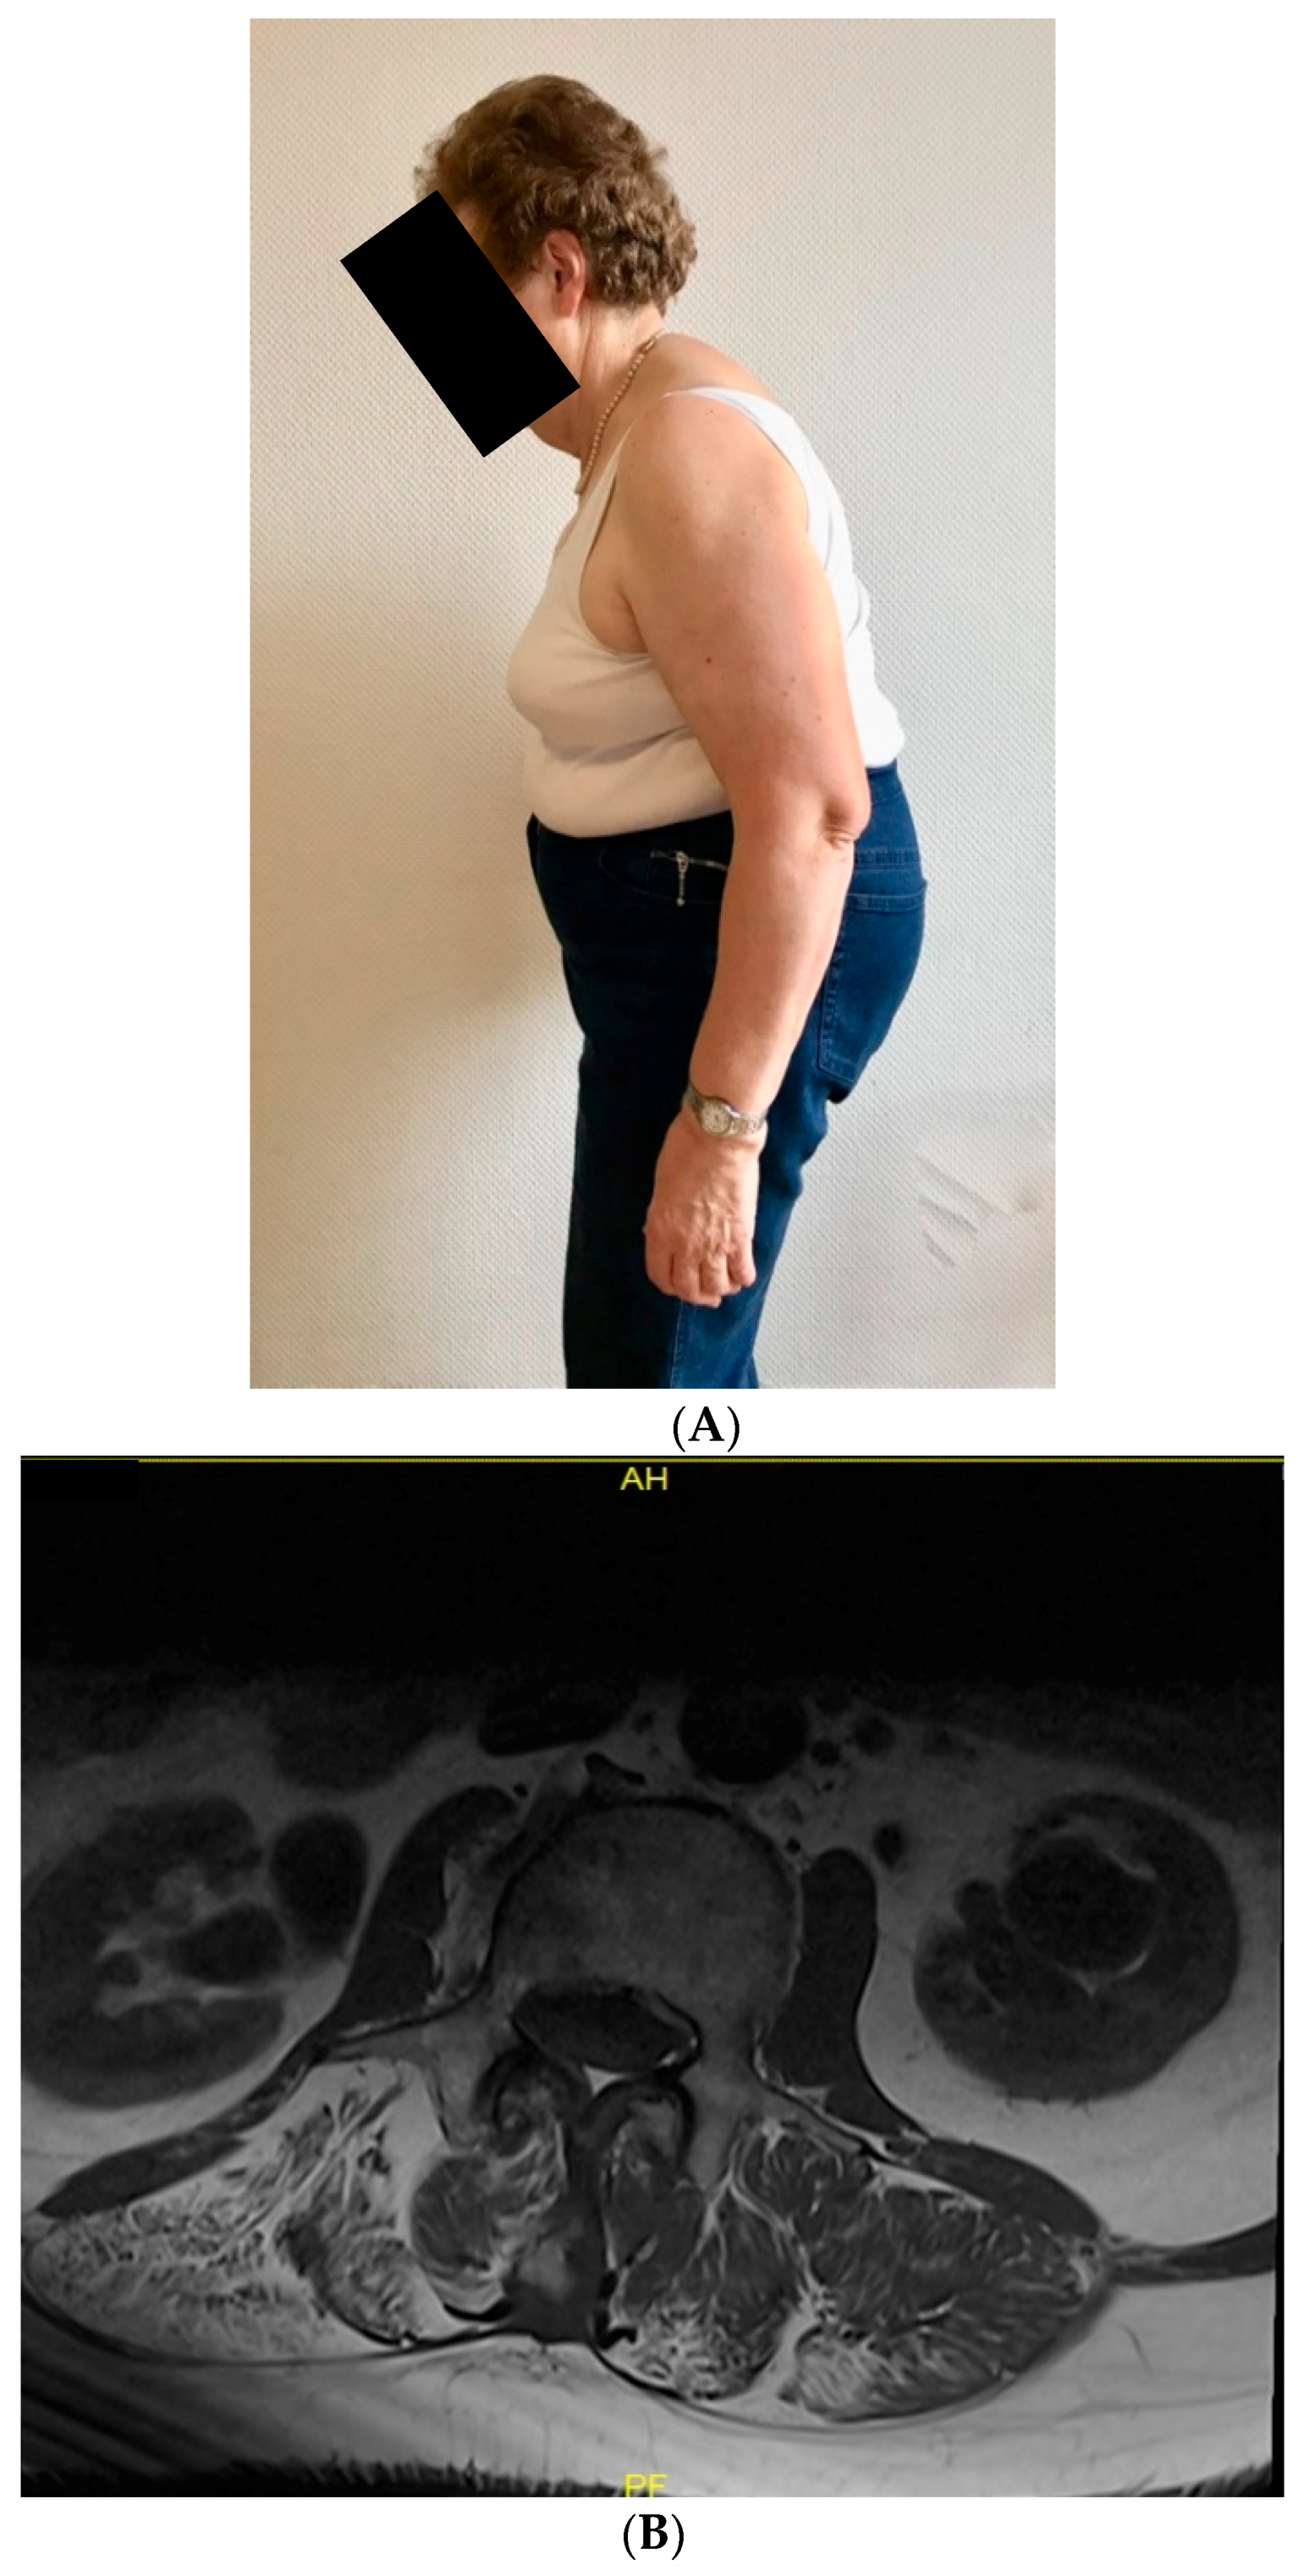

3.1. Clinical Findings and Muscle Biopsy